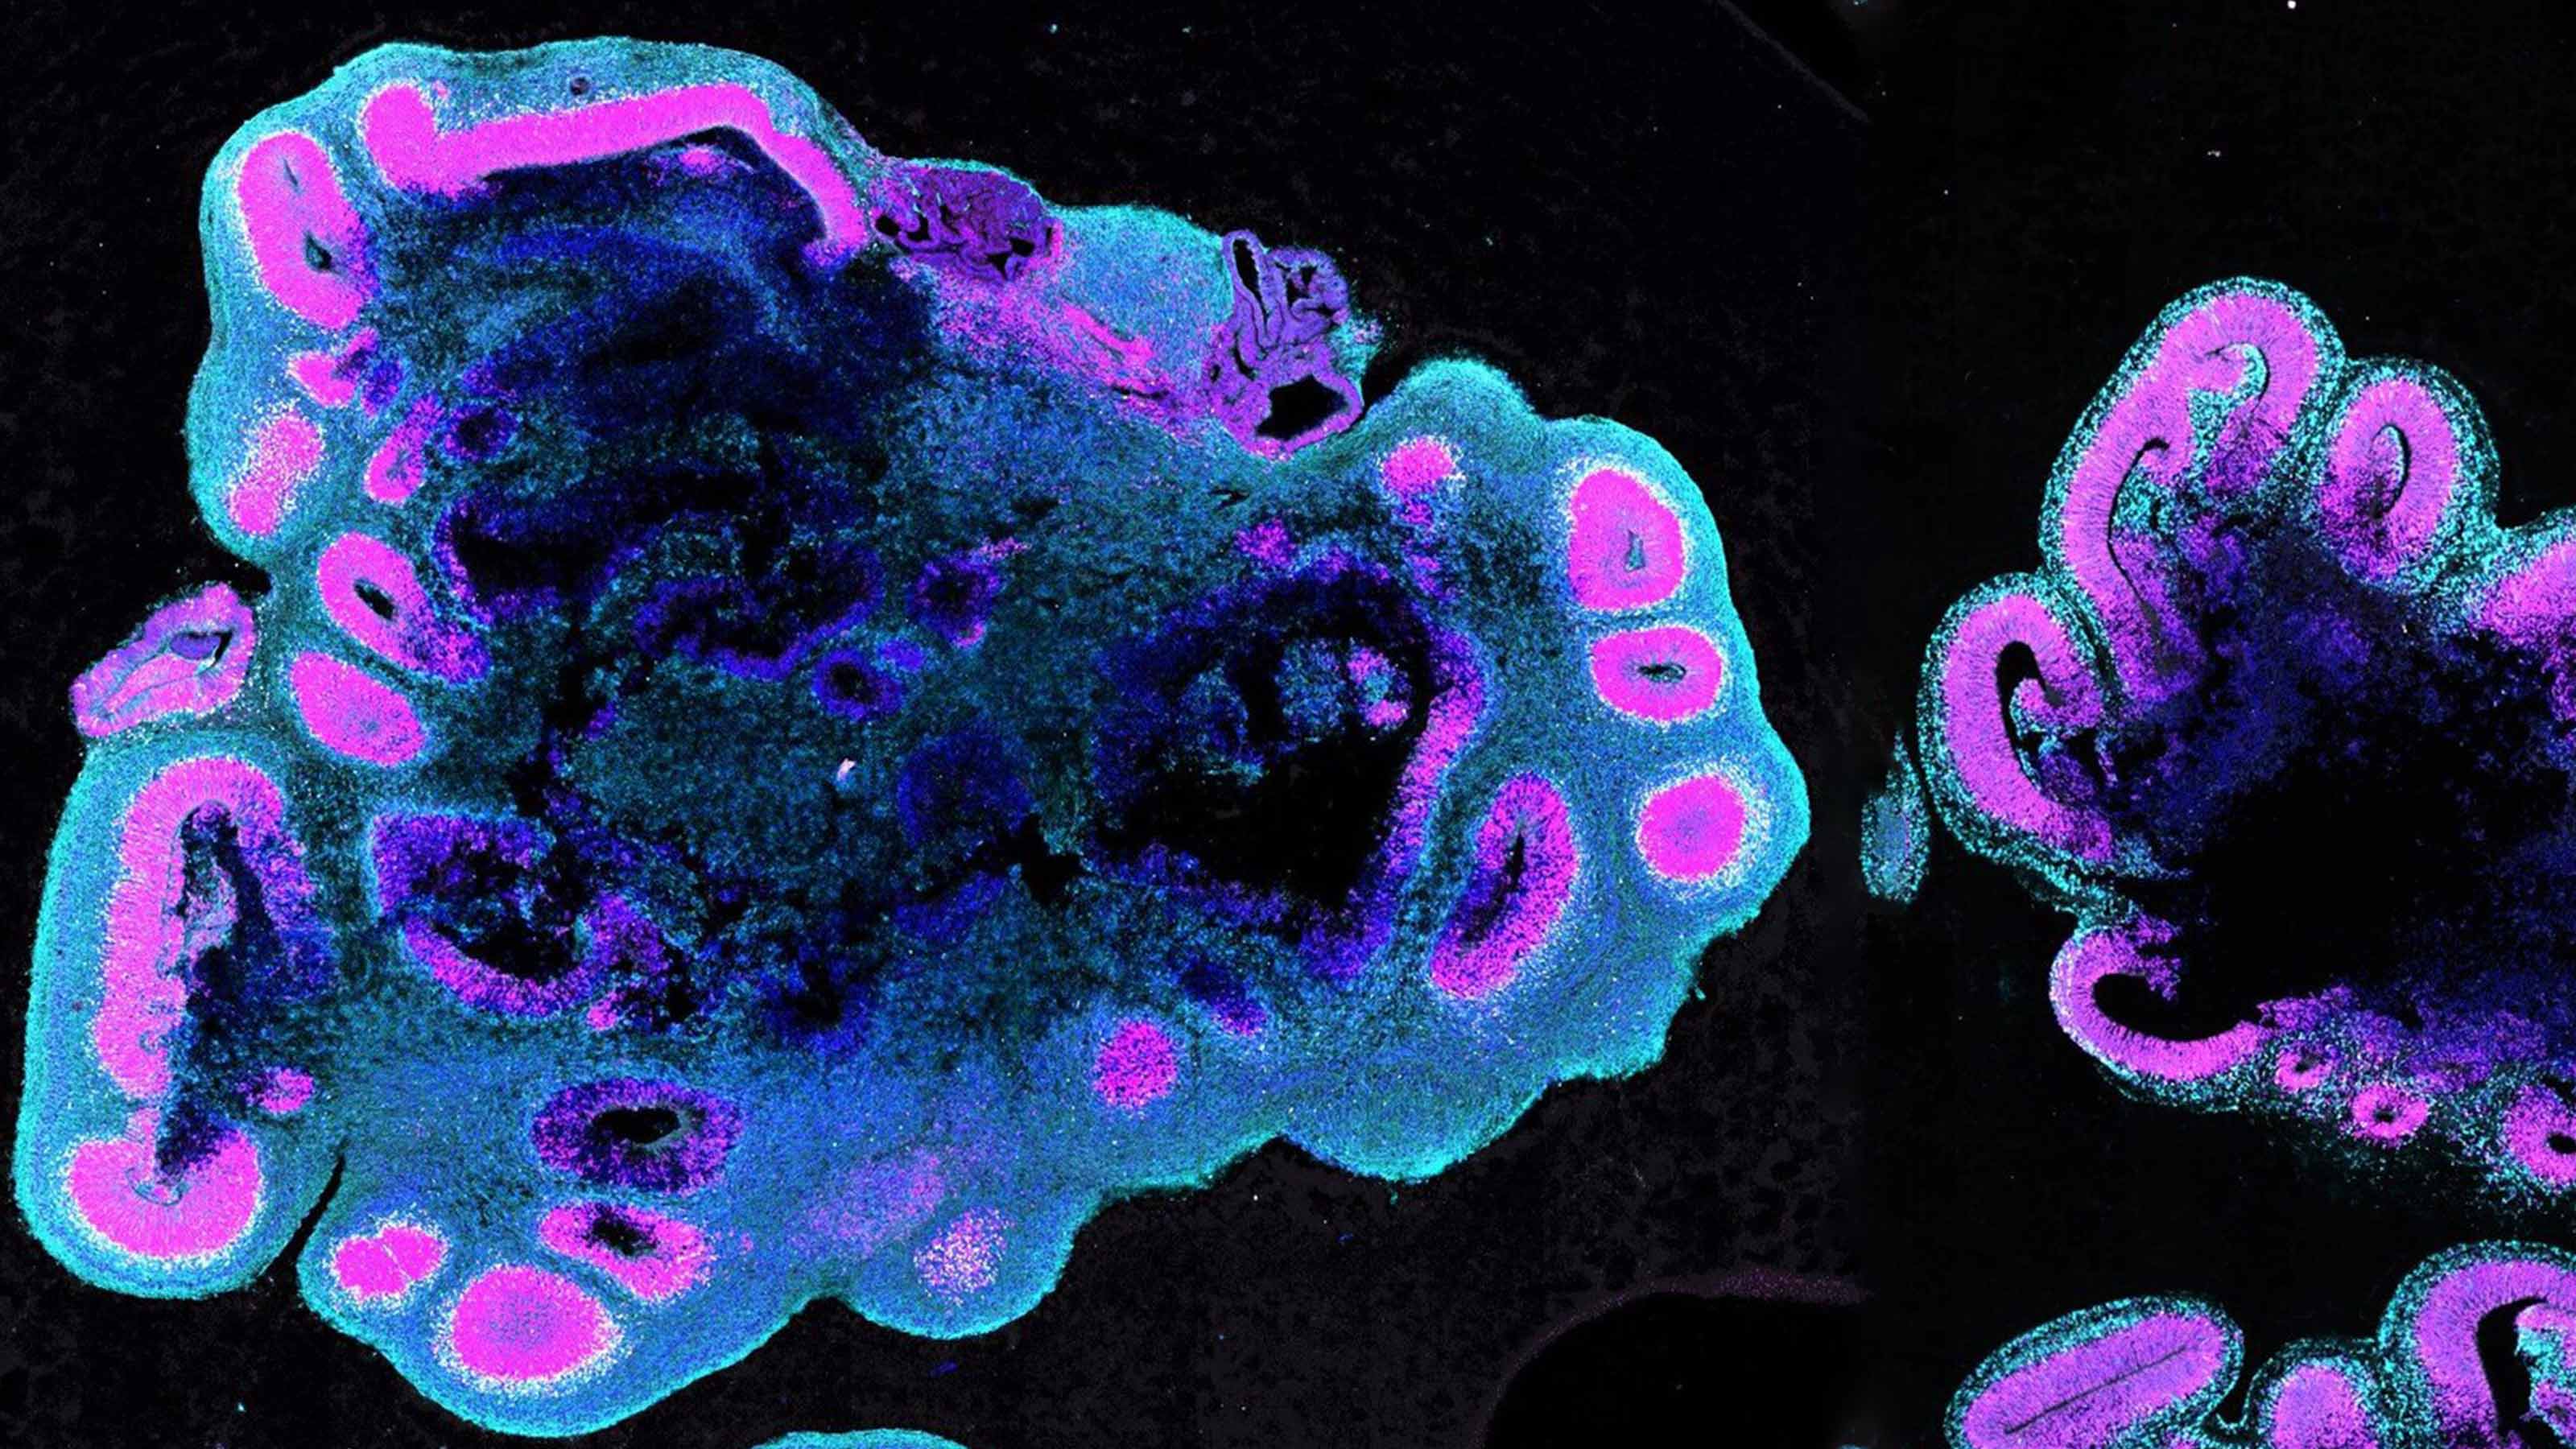

How Arc Institute is bringing science into the century of biology

Researchers at Arc Institute all work toward the same goal: make concrete progress in understanding and treating complex diseases.